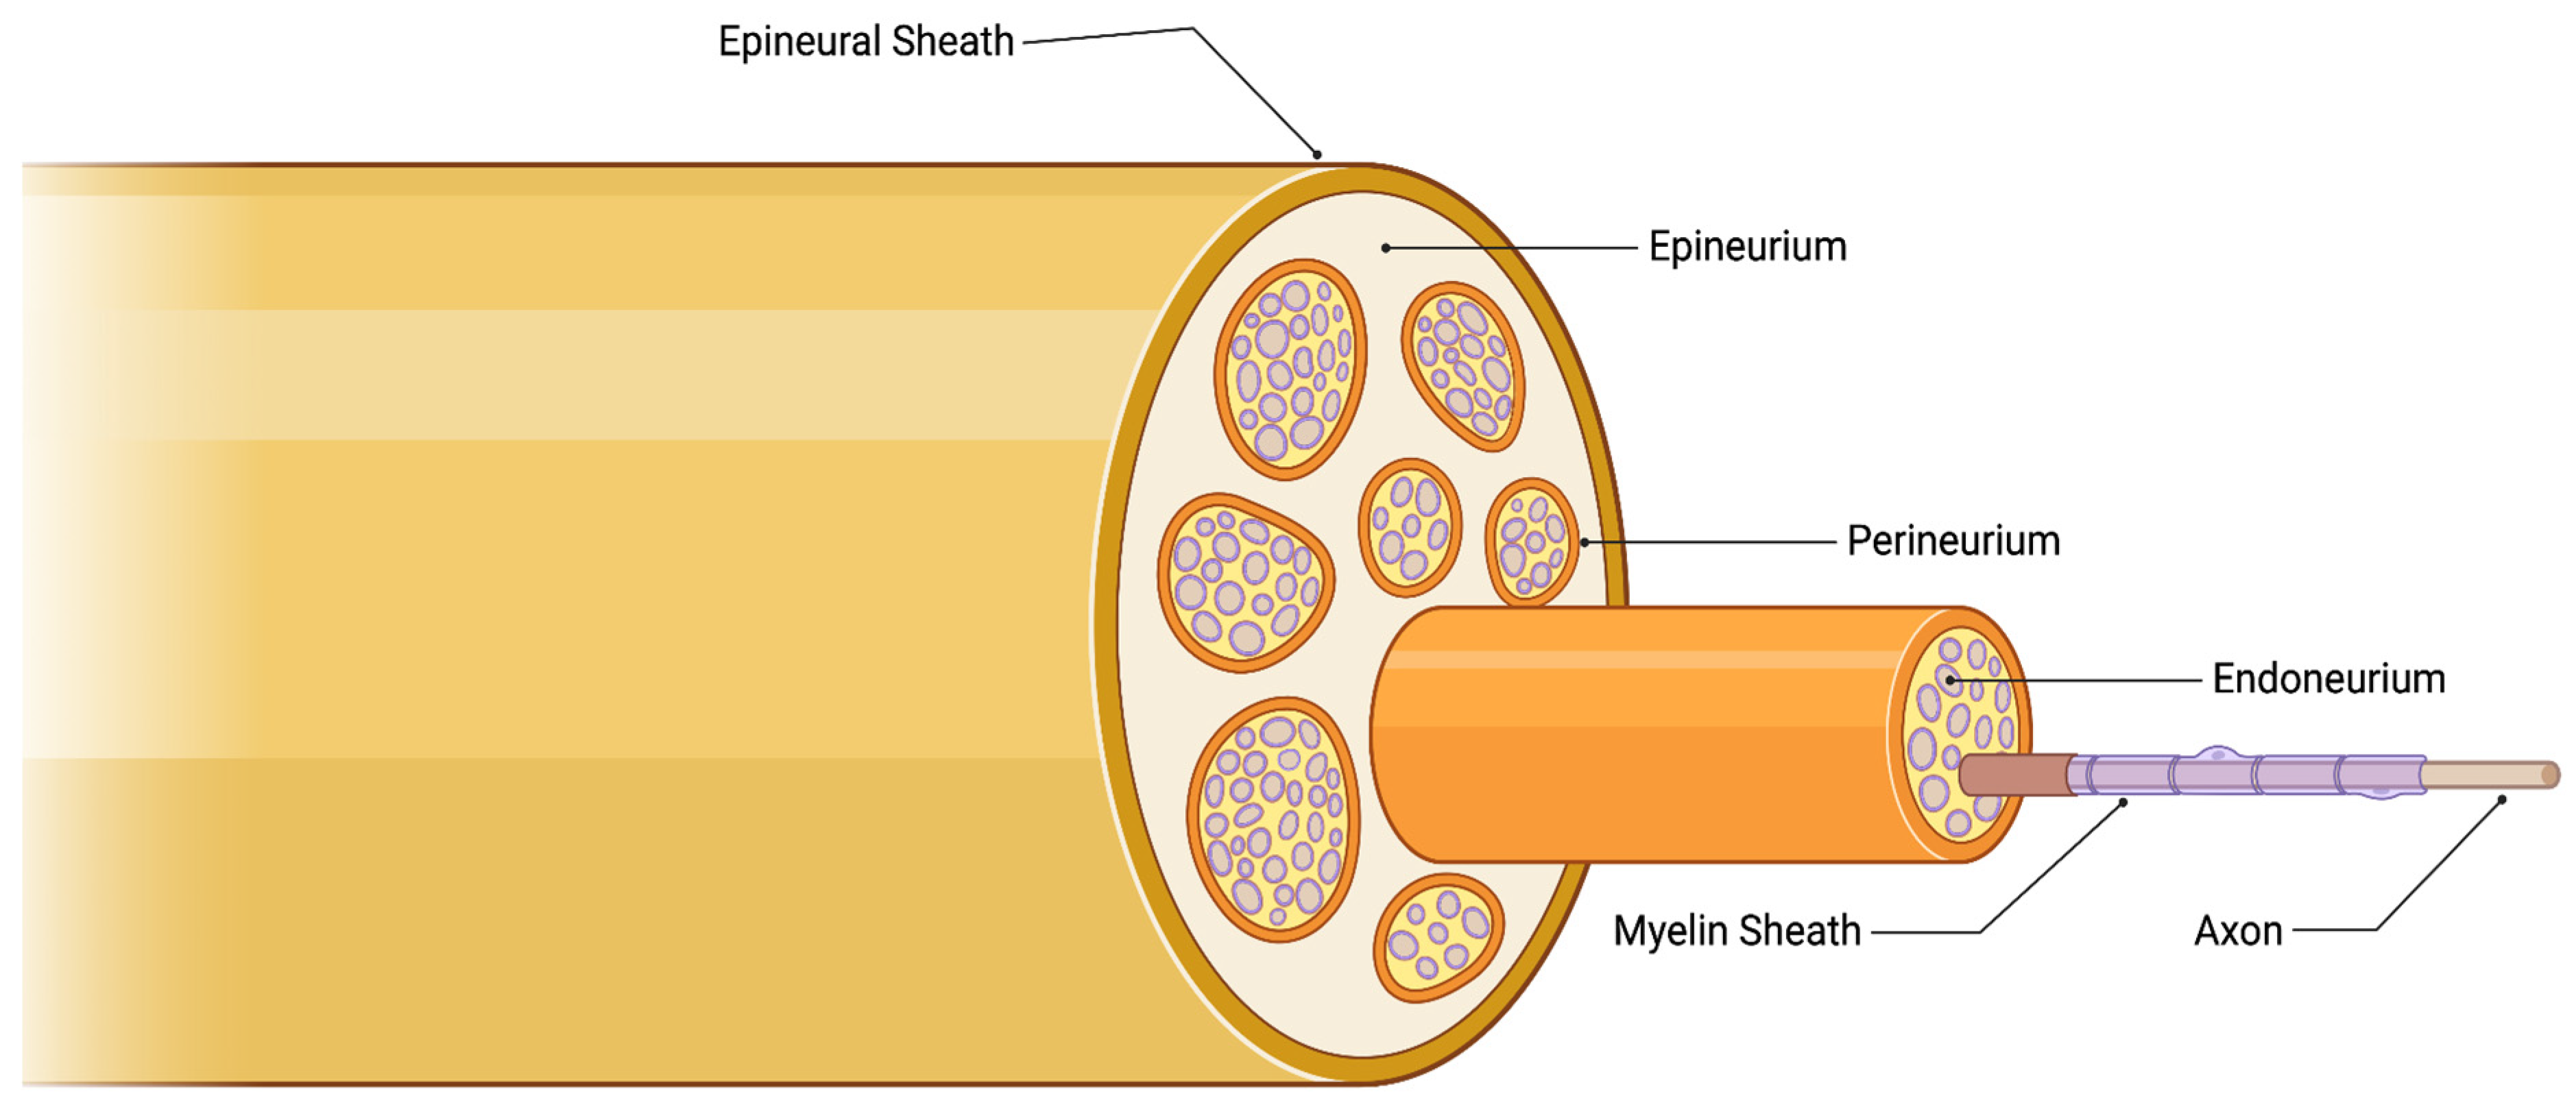

:1. Introduction

2. Signaling Pathways Involved in Inducing Perineural Invasion